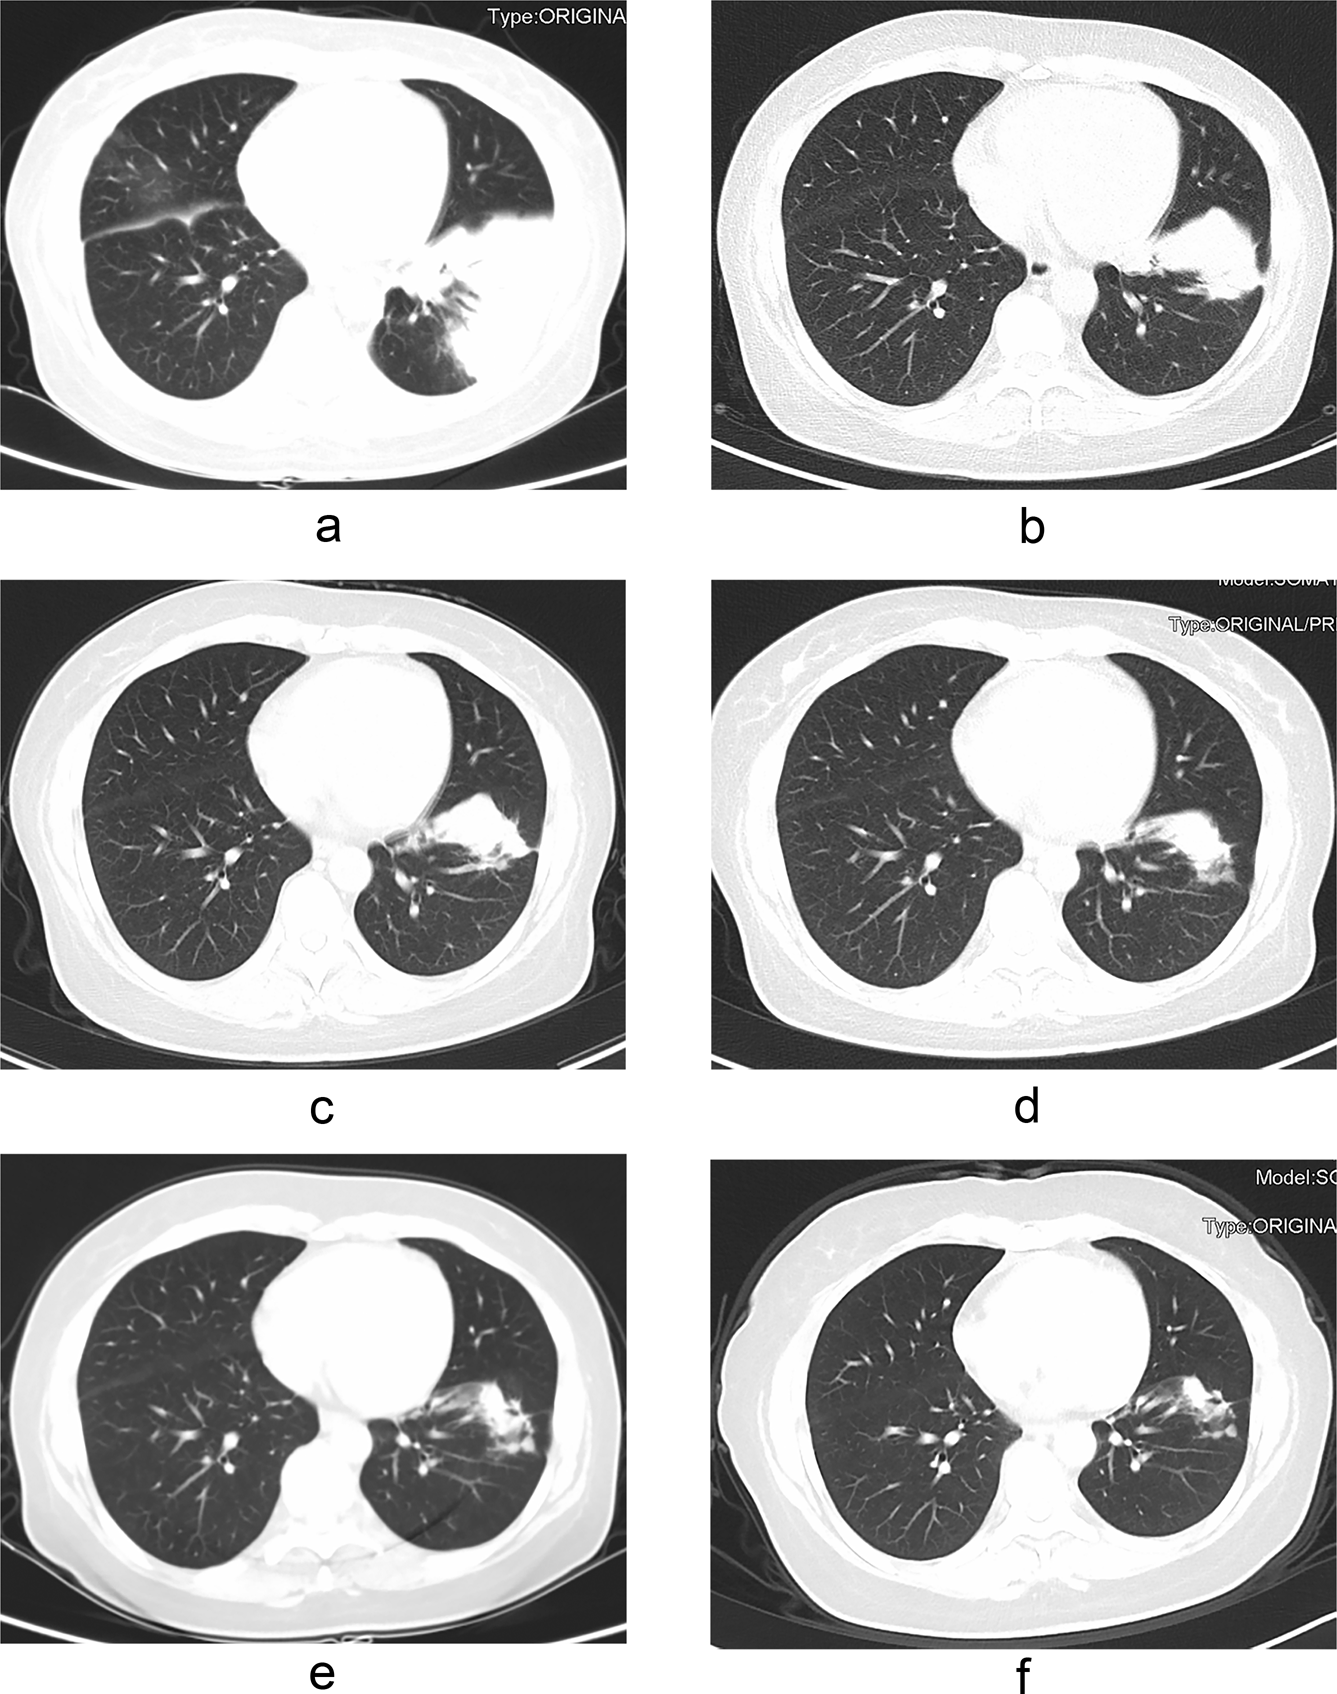

Figure 2

Pulmonary cryptococcosis in a 42-year-old woman with nephrotic syndrome and endometrial cancer after hysterectomy. CT imaging shows patchy consolidation in the left lower lobe of the lung (a). The lesion was significantly reduced after two months of treatment with fluconazole/voriconazole plus 5-fluorocytosine (b). The lesion continued to shrink after five months of treatment (c). The drug was discontinued after 13 months of treatment (d). The focus continued to shrink and there were still irregular soft tissue mass after 16 months (e) and 29 months (f) of drug withdrawal.